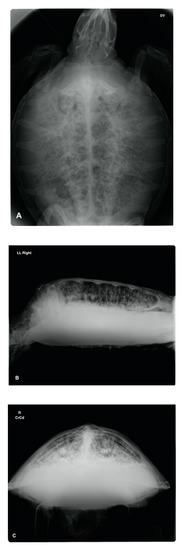

Upon radiographic examination, four of the turtles exhibited severe pneumocoelom. Radiographic signs of pulmonary pathology were seen in all cases; 4 unilateral and 10 bilateral. In these turtles, an increased pulmonary radiopacity, with areas of inhomogeneous parenchyma, interstitial pattern and/or alteration of the pulmonary profile, was found (Figure 1). In one turtle, the radiographic examination showed a reduction of the right lung volume.

During endoscopic examination, one sea turtle showed a tracheal involvement, with a hyperemic and congested mucosa and dense exudate on the ventral surface. In two sea turtles, unilateral or bilateral dense and tenacious exudate at the bronchial bifurcation was found. Caliper reduction of the principal bronchial diameter was found in one sea turtle with abundant muco-purulent exudate. In four sea turtles, an intrapulmonary bronchial involvement of the mucosa was seen, which appeared edematous and congested (Figure 3). Only one case showed a slight deviation in the dorso-medial direction of the bronchial path of the left lung, with evident morphological alteration of the faveoli, which appeared oval and crushed transversely in a ventro-dorsal direction. Out of the 14 sea turtles with evidence of pneumocoelom, 4 underwent a coelioscopy procedure. The ventral surface of the lungs was easily identified during coelioscopy, and positive pressure ventilation highlighted lung trauma and laceration in all four turtles.

Figure 1. Dorso-ventral DV (A), Latero-lateral LL (B) and Craniocaudal CrCd (C) radiographic projection of a Loggerhead sea turtle: bilateral areas of increased pulmonary radiopacity with a reticular pattern (honeycomb) and accentuation of the intrapulmonary bronchi that suggest pulmonary disease.

Figure 3. Bronchoscopic view of the lungs field showing (A) dense exudate in the cranial lung field, leading to caliper reduction of the principal bronchus; (B) intrapulmonary caliper bronchial involvement of the mucosa that appeared edematous and congested, along with morphological alteration of the faveoli.